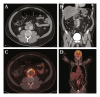

Computed tomography (CT) in axial (A) and coronal (B) view on admission demonstrating a 4.5 cm aortic aneurysm with inflammation of fatty tissue and fluid surrounding the aorta. 18F-fludeoxyglucose (FDG) positron emission tomography/low dose (ld) CT scan in axial (C) and coronal (D) view demonstrating significant heterogeneous FDG uptake of the aortic wall and an increase in diameter of the aortic aneurysm from 4.5 to 5.0 cm. FDG uptake was observed in retroperitoneal lymph nodes most likely reactive to the infected arterial wall. The spleen and bone marrow also showed weak uptake suggestive of an active infection. Physiological FDG uptake was seen in the brain and myocardium with signs of renal tracer excretion.